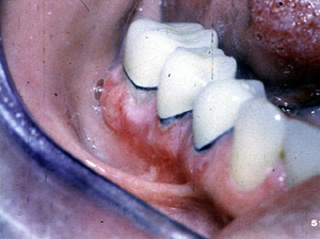

Este paciente es un varón  que está tomando Aldomet  para el tratamiento de la  hipertensión. En esta fotografía usted puede apreciar una úlcera grande en la mucosa bucal. En la periferia de la ulceración hay estrías blancas similares al liquen plano erosivo. Estas ulceraciones son dolorosas y ocurren con la tomo de dicha droga.